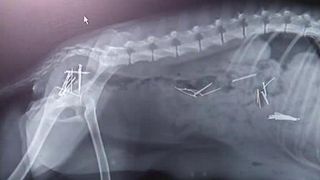

Un act de cruzime cum nici măcar medicilor veterinari nu le-a mai fost dat să vadă vreodată vine din judeţul Arad! O femeie e acuzată că a încercat să-şi omoare câinele punându-i în mâncare 45 de ace cu gămălie! ##VIDEO28213##

Desi proprietara neaga, vecinii o contrazic. Catelusa cu stomacul plin cu ace de gamalie ar fi a ei, iar tot planul diabolic l-ar fi pus la cale ca sa se razbune ca a ramas gestanta. In loc sa o fi sterilizat, femeia ar fi infometat-o, ca sa fie sigura ca bietul animal va inghiti mancarea cu ace.

"A vazut ca este gestanta si a dus-o la clinica, pentru sterilizare si dupa sterilizare au si deparazitat-o si catelusa a vomitat ace de gamalie”, spune medicul veterinar.